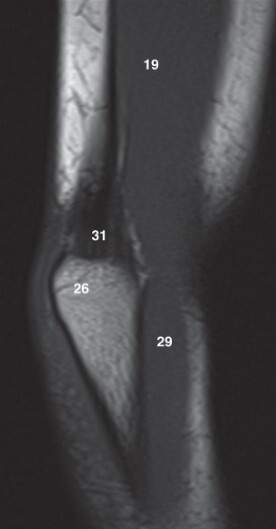

10

Q

Label 19 and 26

A

19-Lt. Triceps brachii muscle

26-Olecranon process of lt. ulna